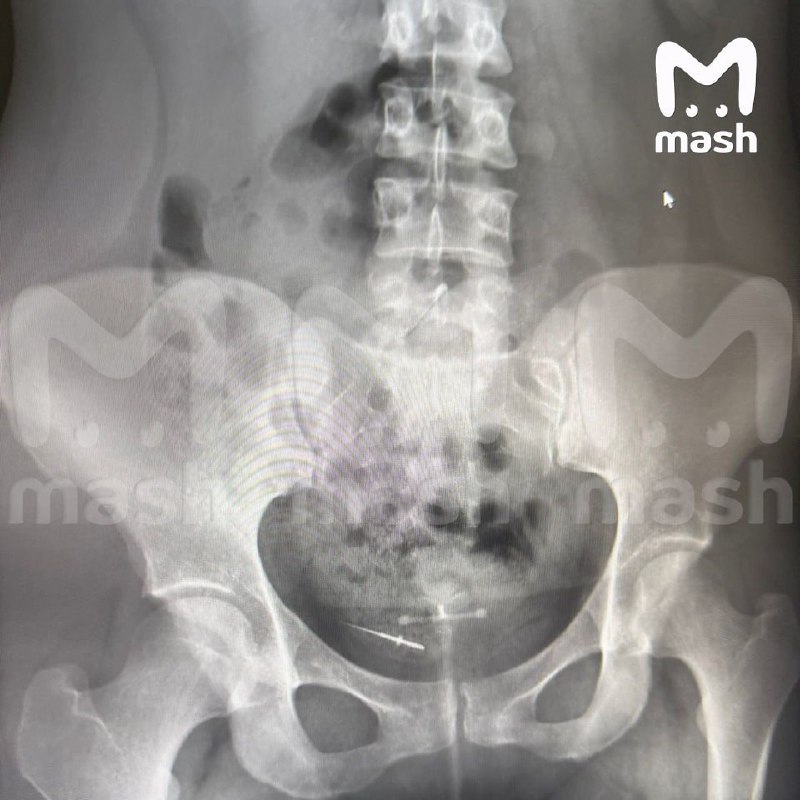

Сразу после лечения зубов 26-летняя девушка почувствовала острую боль в животе. Она сделала рентген, к тому времени протейпер уже мигрировала в нижнюю часть туловища.